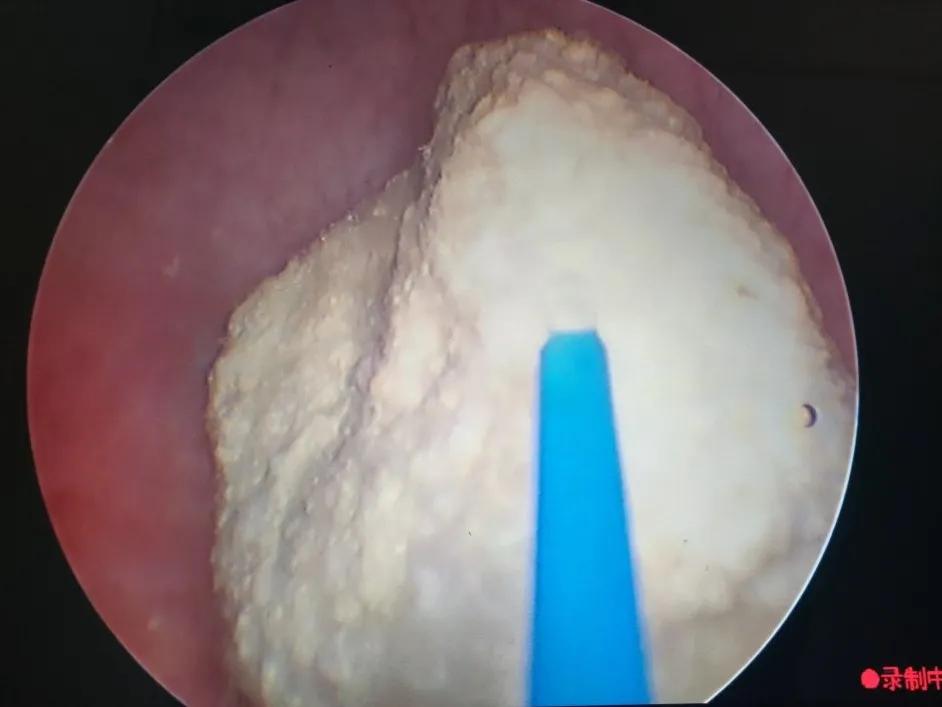

在手术室、麻醉科支持下手术开始,何晓北用钬激光一点点的将两枚结石击打成小碎块,随着结石的去除,节育环渐渐露出了真容,粉红色的两个端头丝毫不像能给患者带来剧烈腹痛的样子。何晓北用激光击打节育环的金属丝,靳永池带领的外一科团队紧盯着屏幕,做好了实施第二、三套方案的准备。随着几次亮光闪烁,节育环成功打断,接着从另一侧取出节育环剩余部分,去除碎石屑,手术顺利,成功结束。